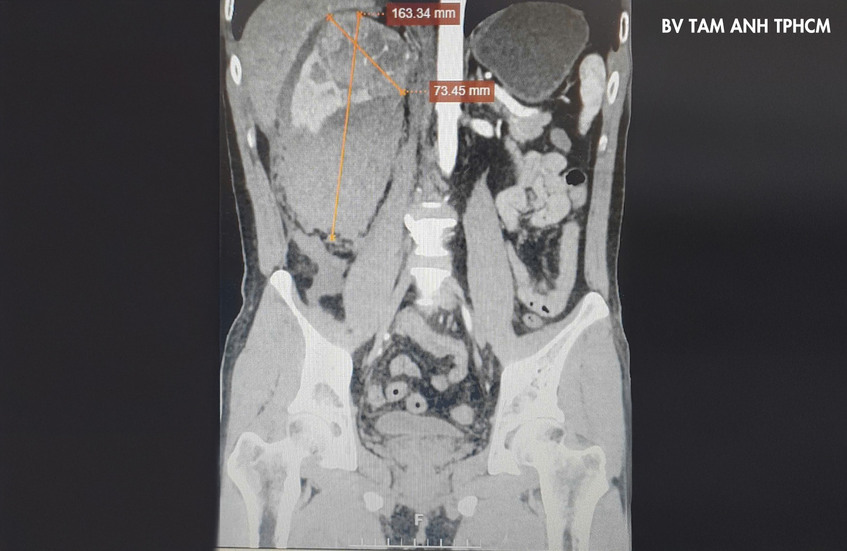

Một tuần trước, anh Nam, 43 tuổi đến Bệnh viện Đa khoa Tâm Anh TP.HCM do đột ngột lên cơn đau ở vùng hông lưng phải, siêu âm thấy bất thường ở thận, bác sĩ chỉ định chụp CT thấy một khối u ở thận phải, kích thước 8cm có tình trạng xuất huyết rất nguy hiểm, nghi ngờ u ác tính. Làm công việc tự do nên anh Nam không có thói quen khám sức khỏe định kỳ, do đó lúc nhận kết quả chẩn đoán, anh ngỡ ngàng bởi từ trước đến nay sức khỏe rất tốt.

Khi tình trạng chảy máu được kiểm soát, TS.BS Lê Phúc Liên, Trưởng đơn vị Niệu nữ, cùng bác sĩ Duy và êkip mổ tạo các vết mổ nhỏ trên bụng của người bệnh, đưa dụng cụ nội soi và bơm khí CO2 vào ổ bụng để tiến hành ca phẫu thuật nội soi. Do khối u quá lớn, không thể cắt u bảo tồn thận, các bác sĩ quyết định phẫu thuật nội soi ổ bụng cắt thận, u thận vỡ và bóc trọn khối máu tụ quanh thận thành một khối, tránh nguy cơ lan tràn tế bào ung thư nếu là ác tính. Túi bệnh phẩm lấy ra khỏi cơ thể người bệnh được đưa đi phẫu tích, một tuần sau cho kết quả ung thư biểu mô tế bào sáng (ccRCC), giai đoạn T2a.